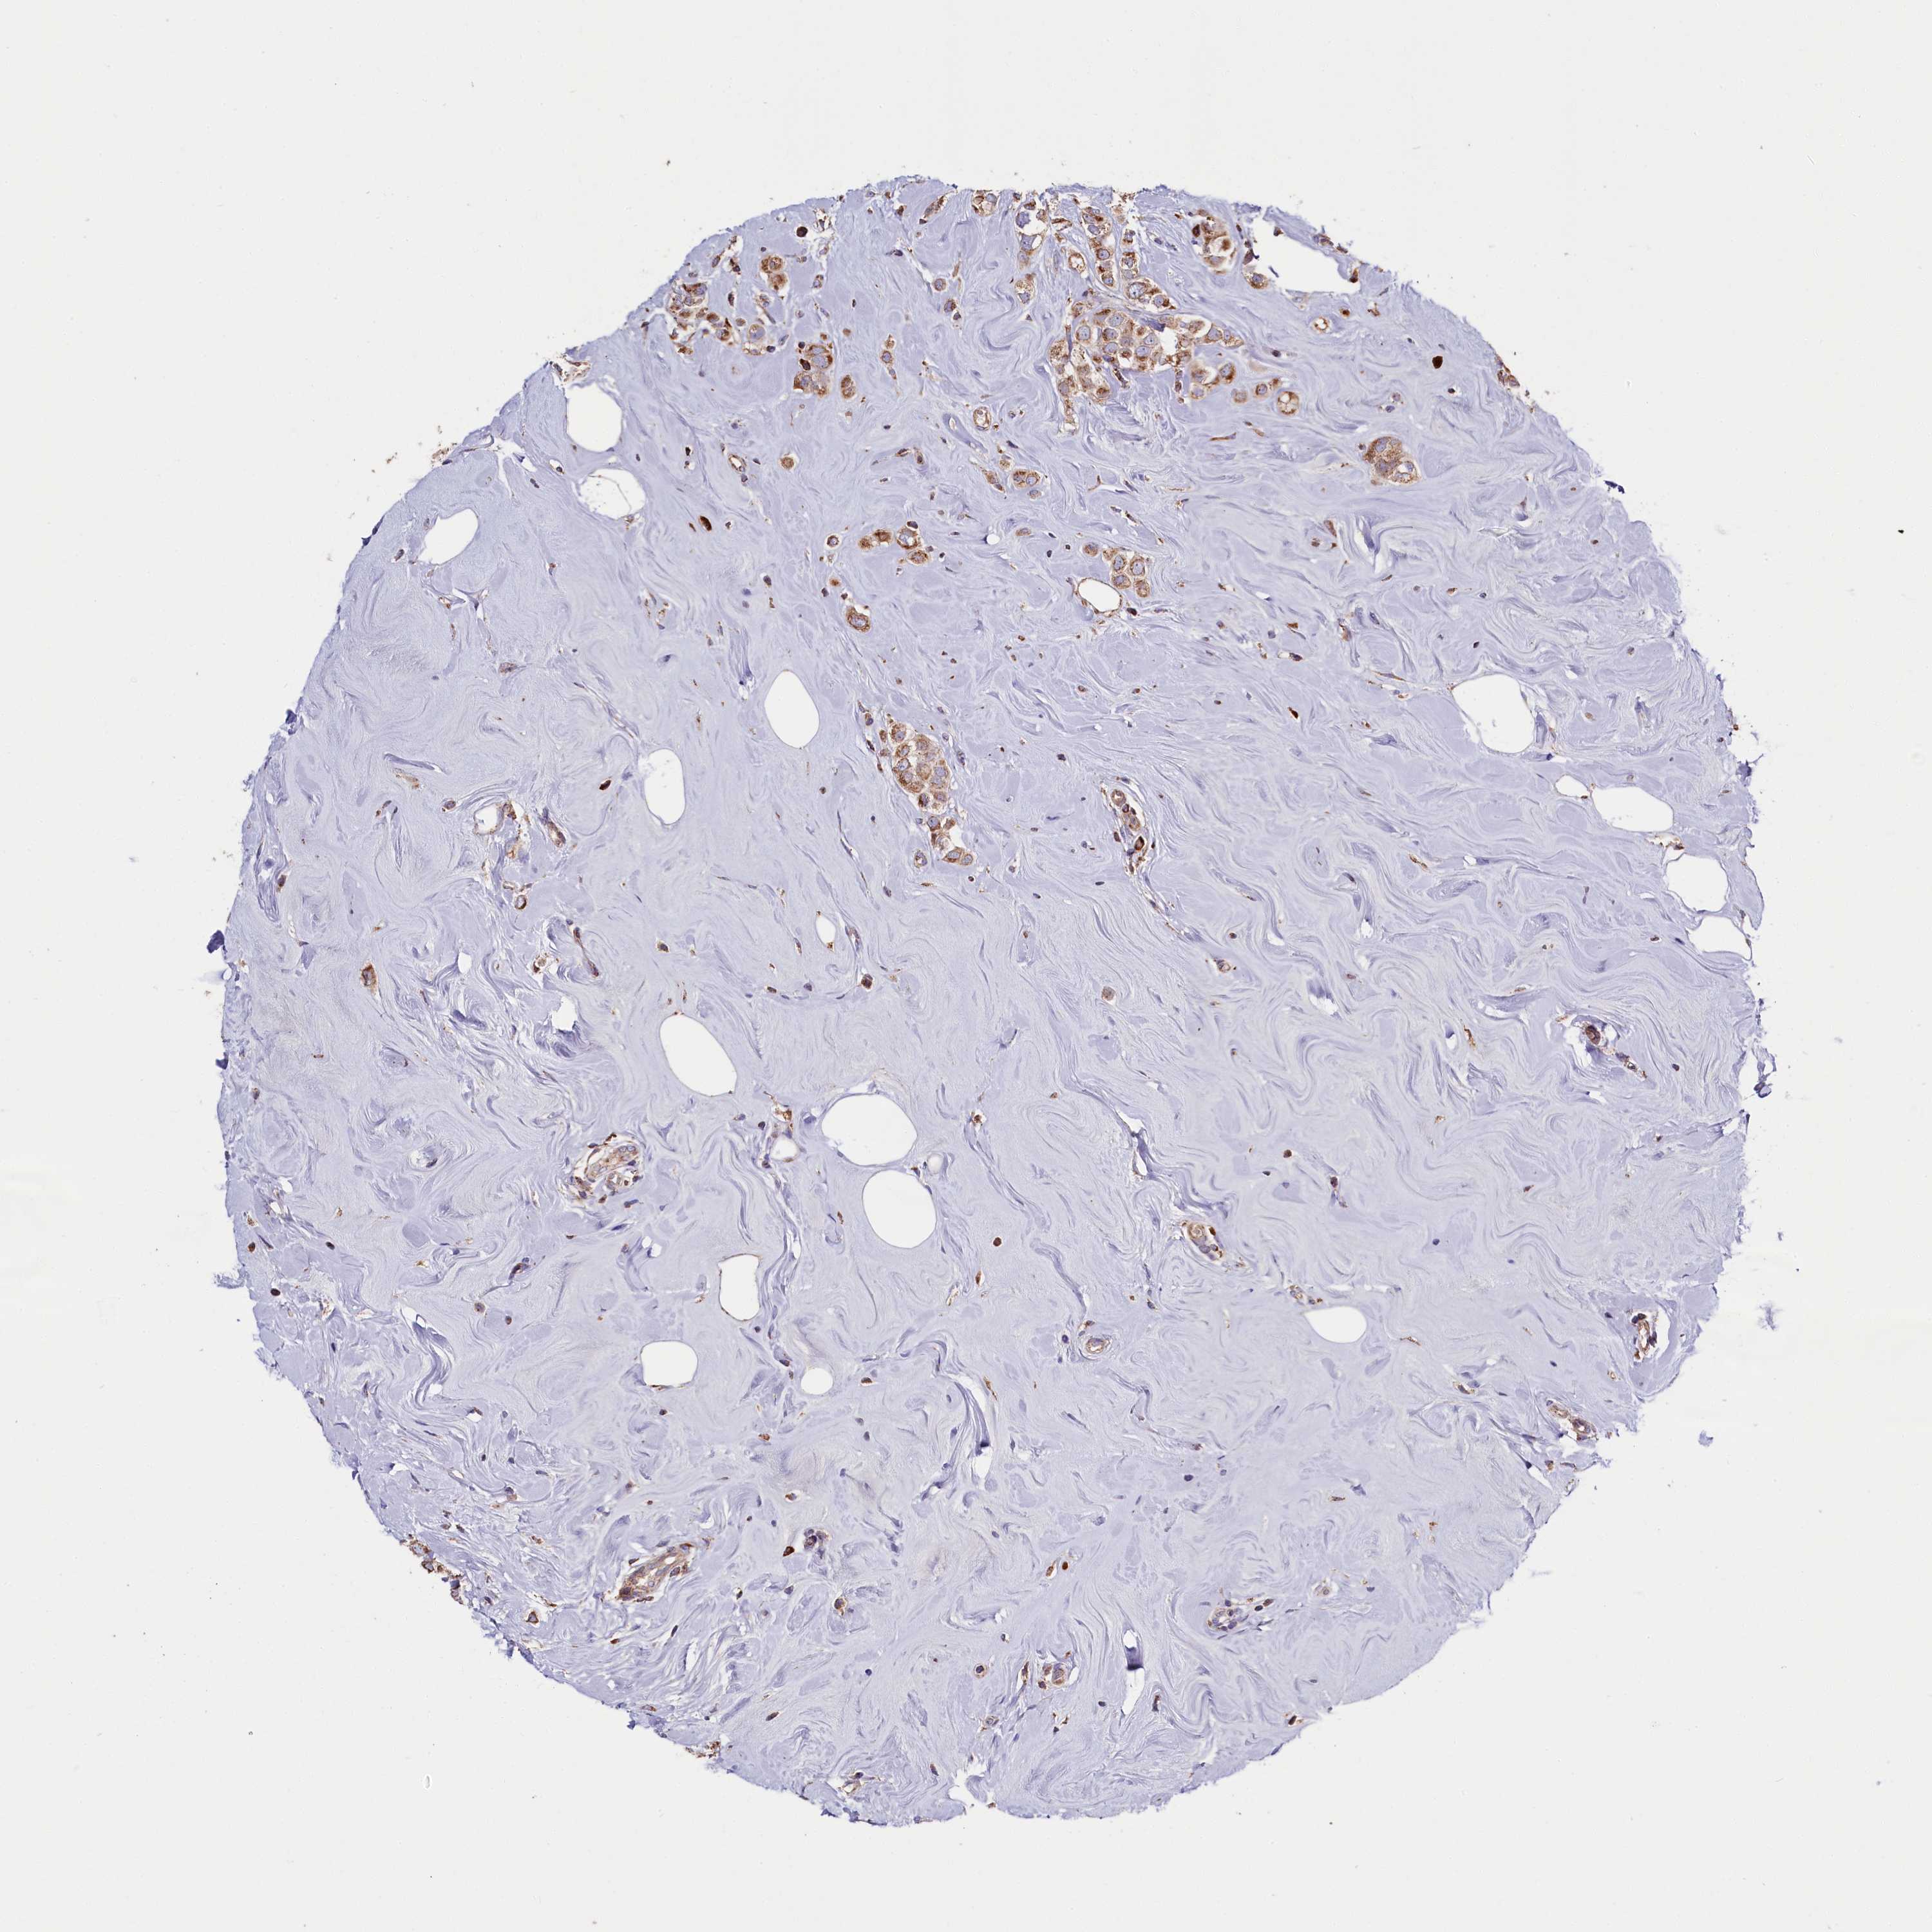

CANCER BREAST CANCER Show tissue menu

Breast cancer

Human cancer